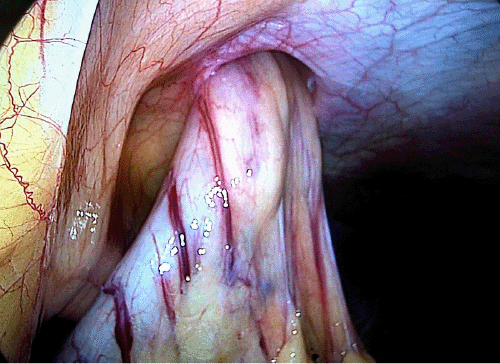

The patient ultimately underwent a laparoscopic approach with a reduction of the gastric hernia and repair of the hernia defect with biologic mesh underlay (Figure 2 and Figure 3). Primary repair of the hernia defect was deferred due to the size of the defect. An endoscope was then passed into the stomach for direct visualization and placement of a new gastrostomy tube. The resultant gastrocutaneous fistula present from the prior herniated defect was then taken down by an external dissection, including the removal of the entire hernia sac. The subcutaneous tissue tunnel was closed primarily.

Figure 2. Intraoperative View of Gastric Herniation Through Abdominal Wall Defect. Published with Permission

Figure 3. Intraoperative Repair of Hernia Defect with Biologic Mesh. Published with Permission